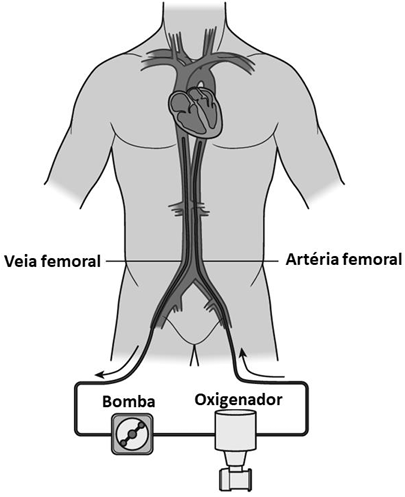

Os dispositivos de assistência circulatória apresentam papel fundamental no manejo de pacientes com choque cardiogênico em diversos cenários clínicos.

A respeito do tema, considere a seguinte figura.

Um potencial cenário de instabilidade hemodinâmica com contraindicação absoluta ao sistema de suporte circulatório demonstrado na figura é a